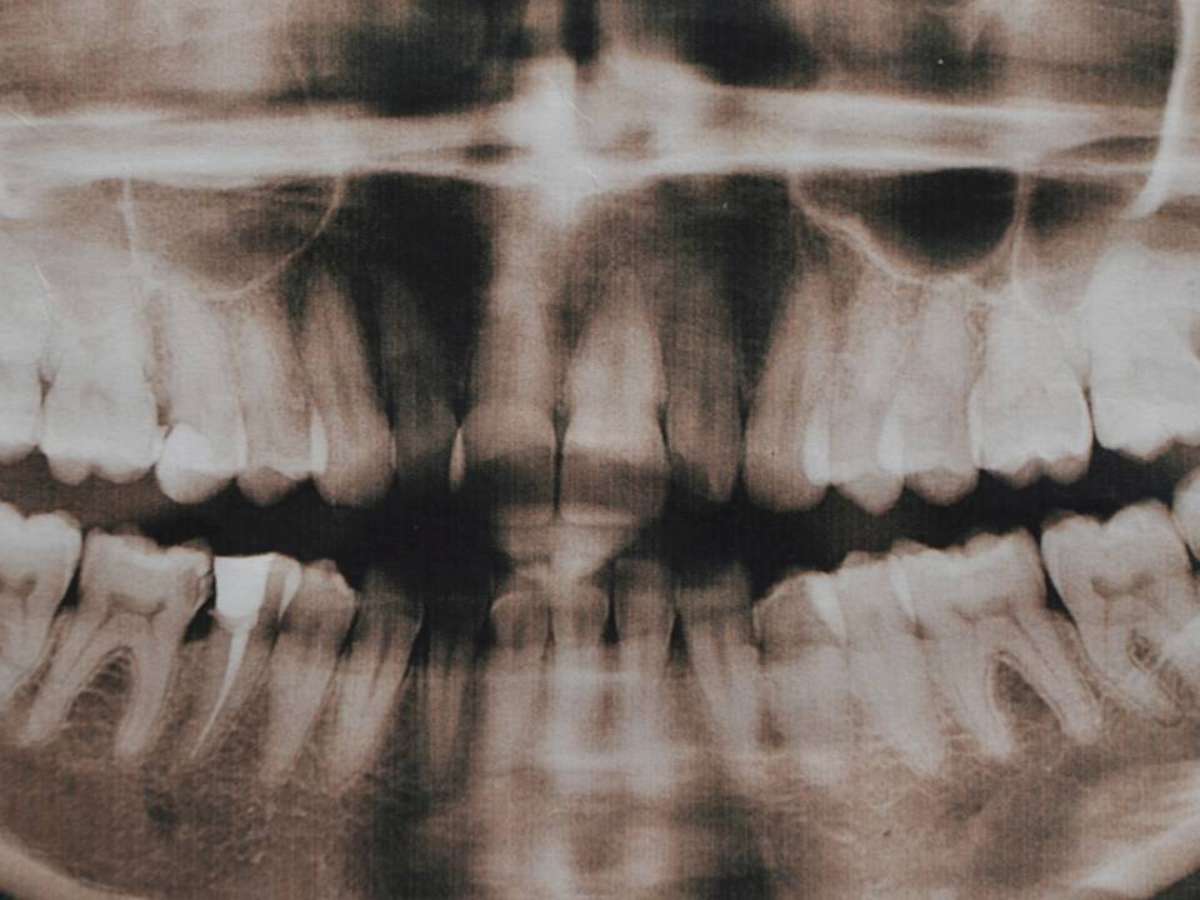

A hiperdontia é uma alteração do desenvolvimento dentário em que surgem dentes extras, os dentes supranumerários – depositphotos.com / YuliyaM

Clinicamente, a hiperdontia pode causar atraso na erupção dos dentes permanentes, desalinhamento, mordida cruzada e, em alguns casos, dor ou inchaço. Quando esses dentes supranumerários permanecem presos dentro do osso, a detecção costuma ocorrer em exames de rotina, como radiografias panorâmicas. Nestes casos, os dentistas as solicitam para acompanhar o crescimento craniofacial, principalmente na infância e adolescência.